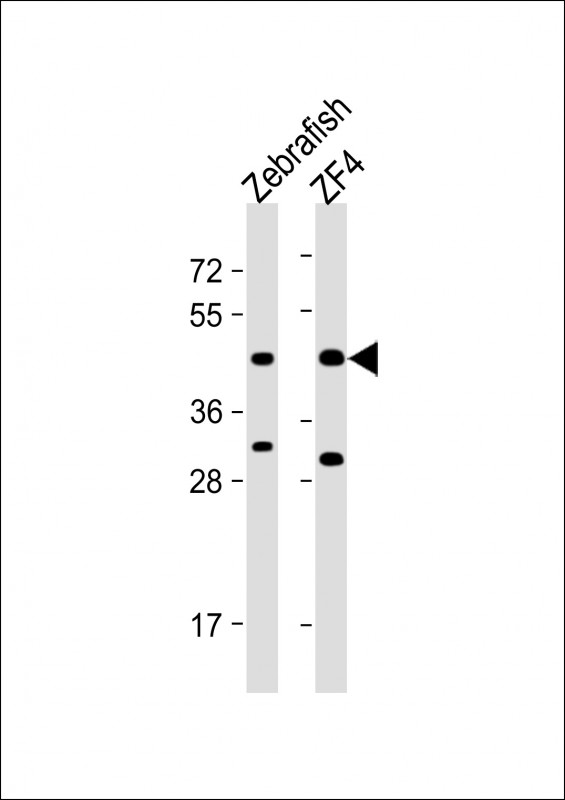

- Immunohistochemical analysis of paraffin-embedded human cerebellar tissues using BRAF mouse mAb with DAB staining.